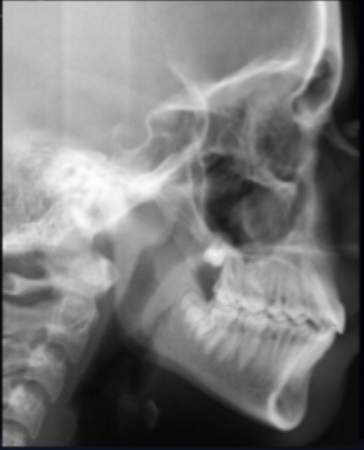

<p>what class of occlusion is shown in this x-ray? </p>

what class of occlusion is shown in this x-ray?

class I (x-ray)